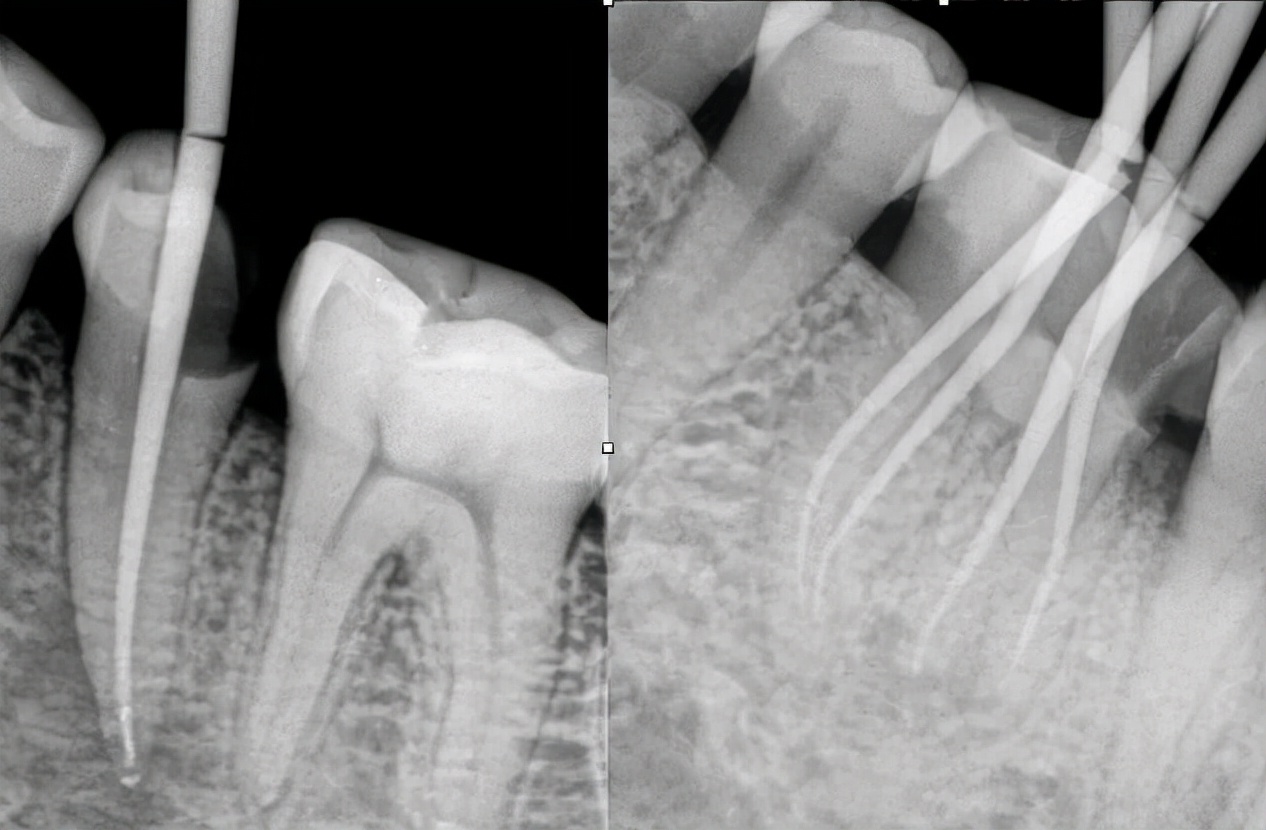

一般情况下,患有根尖炎症都是需要进行根管治疗,清除根管神经等受到感染发炎的组织,同时对根尖进行填充,隔绝空气,预防二次感染。

定期的口腔检查有助于提前知晓牙齿的情况,尤其是根尖炎,初期一般无法发现病症,在拍片检查的时候是能够较好地知悉口腔情况。